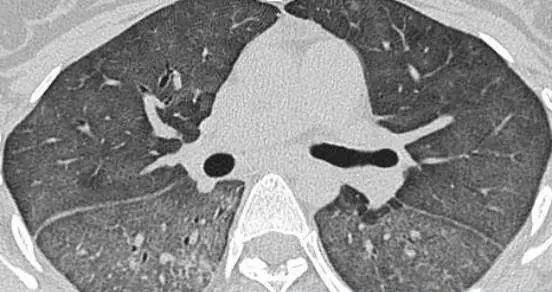

外源性过敏性肺泡炎肺部影像

为寻求进一步诊治,张先生来到了我院。呼吸与危重症医学科宋刚主任详细审阅了张先生的肺部CT片和相关检验报告,并询问了接触史,最终确诊张先生患有外源性过敏性肺泡炎

外源性过敏性肺泡炎(HP),也称过敏性肺炎,是一种由反复吸入某些具有抗原性的有机粉尘所引起的过敏性肺部炎症。过敏性肺炎比较明显的特征就是间质性肺炎、肉芽肿、细支气管炎,其症状包括咳嗽、咳痰、呼吸困难、发热、乏力和胸痛等,影像学表现为弥漫性肺部改变,以中上肺叶为主。